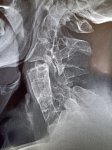

Аноним 16/10/25 Чтв 08:22:29 #3 №325598833

IMG20251016101810.jpg

Где пиздецома?

>>325598813

что за пятно в мозге?

>>325598844

Это дырка в кости же

Аноним 16/10/25 Чтв 08:58:50 #15 №325599636

>>325599617

Аноним 16/10/25 Чтв 09:07:34 #18 №325599870

>>325599775

Аноним 16/10/25 Чтв 09:17:43 #25 №325600106

>>325600080

>>325599918

Оператор лаборант же, он фоткает я описываю.